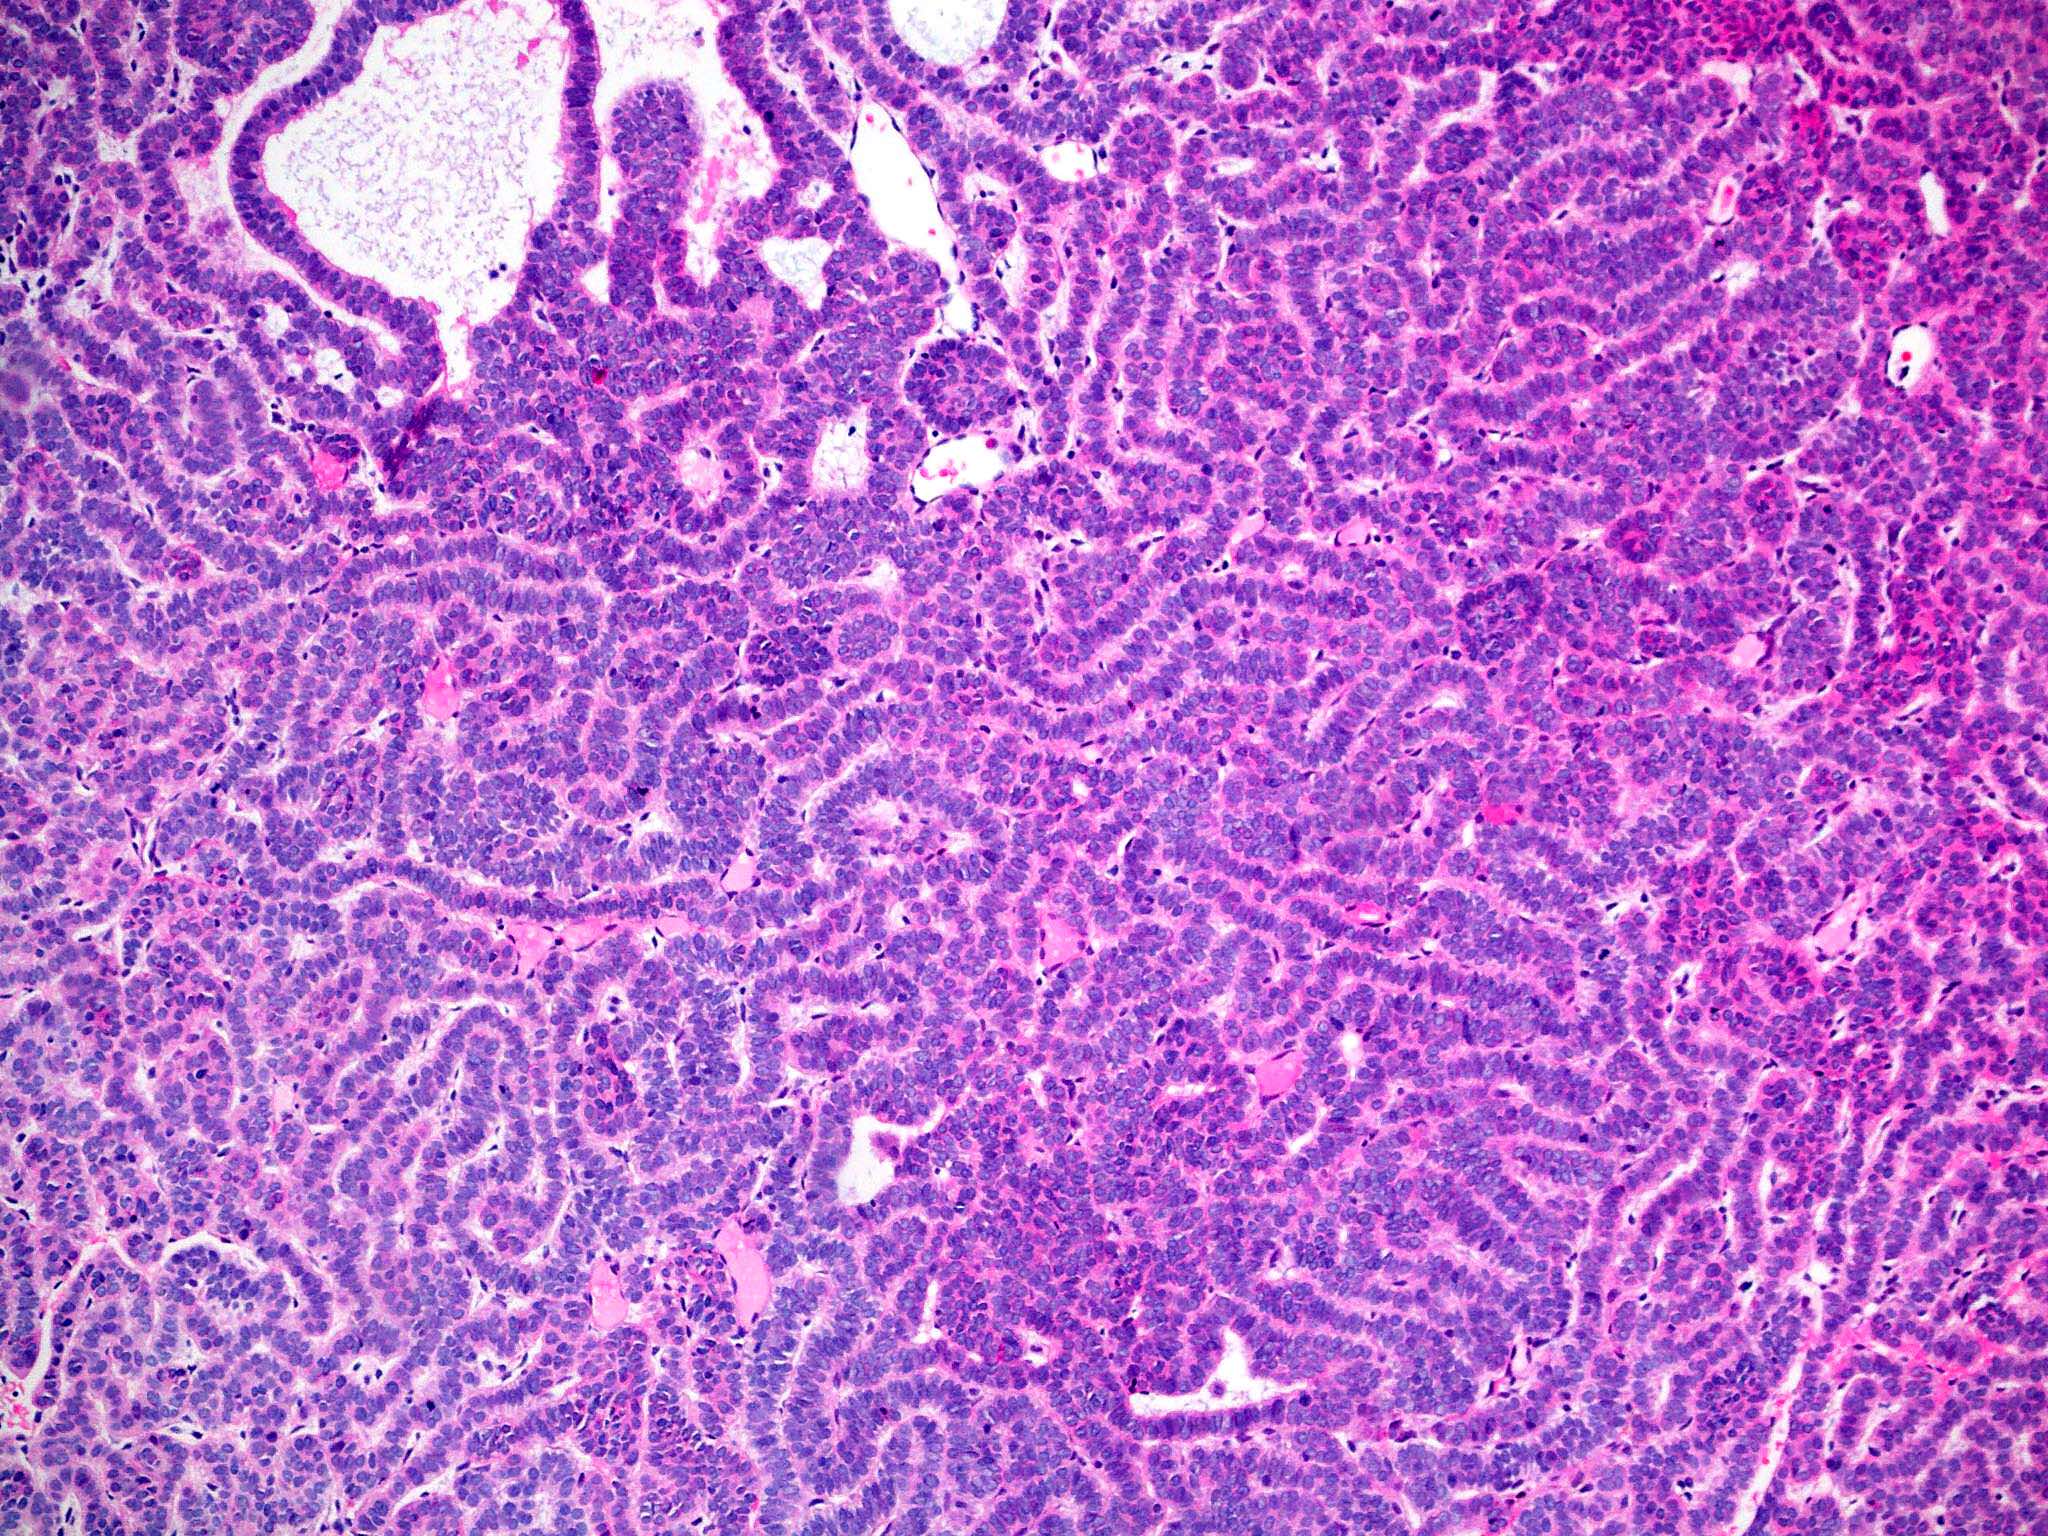

- Nodular and nodulocystic BCC

- Relatively circumscribed mass

- Epidermal or follicular attachment variably present

- Large basaloid lobules with peripheral nuclear palisade

- Lobules may be solid or show central cyst formation due to excessive mucin production

- Fibromyxoid stroma

- Cleft formation between tumor lobules and stroma

- Pleomorphism is generally mild

- Variable mitotic activity and apoptosis

- Sometimes necrosis en masse

Microscopic (histologic) images

Contributed by Antonina Kalmykova, M.D., Phillip H. McKee, M.D., Sate Hamza, M.D., Eduardo Calonje, M.D.,

Wayne Grayson, M.B.Ch.B., Ph.D., James Sampson, M.B.B.S., M.Sc. and Assia Bassarova, M.D., Ph.D.